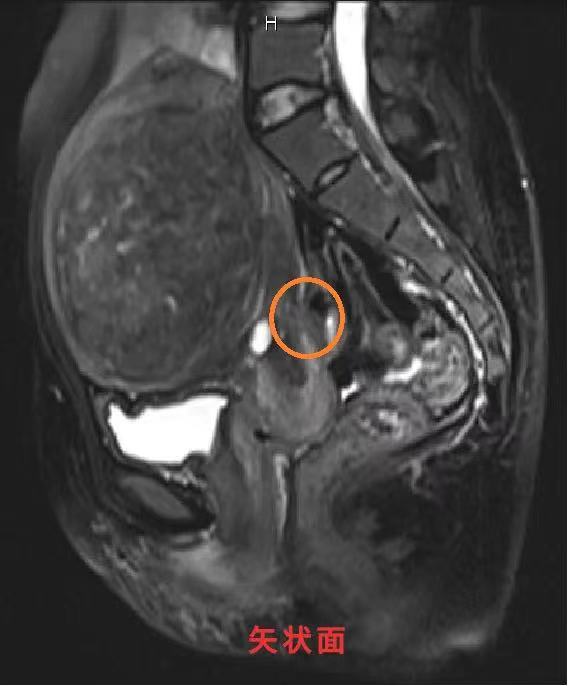

以上3张图(矢状面、冠状面、横断面)中圈出位置可见MRI:子宫后壁近宫颈处见结节状短T1信号。